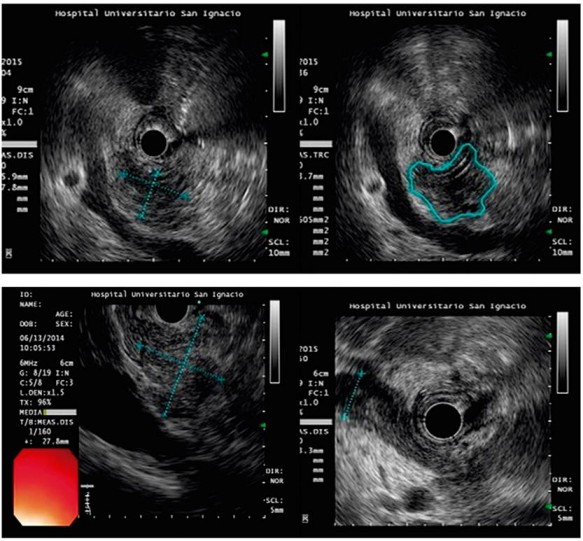

Como se mencionó, la USE es particularmente ideal para las lesiones <2 cm o cuando existe una sospecha clínica de cáncer de páncreas, en la cual otras modalidades han fallado en identificar una masa y en obtener una confirmación histológica (Figuras 1A y 1B). En este contexto, la USE es considerada la técnica de imagen más sensible para la caracterización de los tumores pancreáticos, ya que alcanza valores reportados en la literatura del 89 al 100 % para la detección del adenocarcinoma de páncreas 5,6,7.

A pesar de la alta sensibilidad de la USE, sigue siendo difícil diferenciar el adenocarcinoma del páncreas de otros tipos de lesiones sólidas, al considerar solo las características endosonográficas 7,10. En este sentido, la utilización de la elastografía y los contrastes ha permitido la caracterización de patrones que mejoran la sensibilidad visual de las imágenes, así como la orientación en la toma de la biopsia, para obtener el tejido y lograr la confirmación histológica de las lesiones, la cual es indispensable a la hora de decidir medidas terapéuticas.